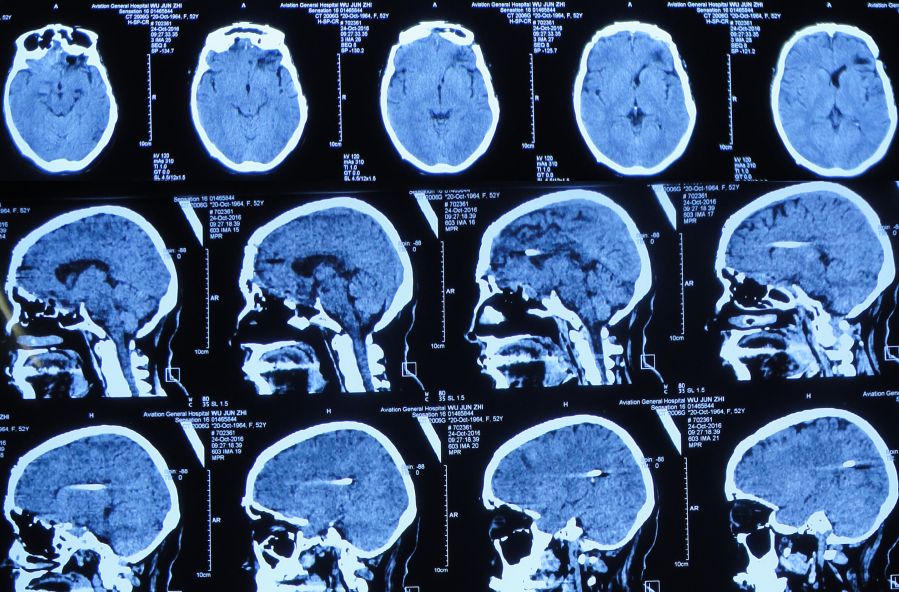

胆囊造瘘术后第56天即2015年12月25日,复查头CT:颅内无异常(图44)。查腹部CT:胆囊造瘘术后,改变(图45)。

图44:2015年12月25日头CT:颅内无异常